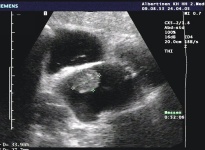

Das Mesotheliom ist ein Tumor der zum Beispiel von Zellen des Lungenfells des Bauchfells oder des Herzbeutels ausgeht und die Lunge mantelförmig umschließt. Oft wird es bei einem Herz-Ultraschall erkannt.